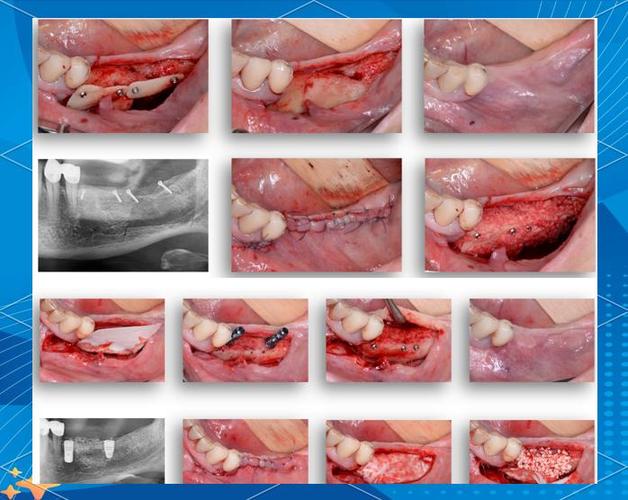

牙槽骨是支撑种植体的“地基”,若骨高度、宽度或密度不足,种植体易松动、脱落,甚至引发感染,骨粉的主要作用是填补骨缺损,引导成骨细胞附着、增殖,促进新骨形成,最终实现“骨结合”(种植体与自体骨融合),临床常用的骨粉包括自体骨(患者自身取骨)、异种骨(如牛骨、猪骨,经脱蛋白处理)、人工合成骨(如羟基磷灰石、磷酸三钙)等,其中异种骨因来源充足、成本较低,应用较广,但需确保其生物相容性和无免疫原性。

- 骨粉吸收与新骨形成:异种骨粉在植入后2-4周开始被巨噬细胞、成骨细胞分解,同时自体骨细胞在骨粉表面沉积,形成新骨,这一过程缓慢,通常3-6个月通过CT检查可见骨粉被新骨替代,密度接近自体骨。

伤口裂开或骨粉暴露

- 症状:牙龈切口裂开,骨粉外露,呈白色或颗粒状,可能伴疼痛、出血。

- 原因:术后咬合创伤、口腔清洁不当(如用力刷牙、漱口过猛)、或缝合不牢固。

- 处理:小范围暴露可进行口腔消毒(如氯己含漱液),避免感染;若裂开较大,需重新缝合,必要时取出暴露的骨粉。